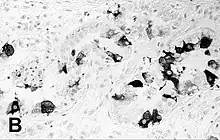

![]() | |

| Encephalitis in the cerebral cortex of a harbor seal with PDV, stained with hematoxylin and eosin | |